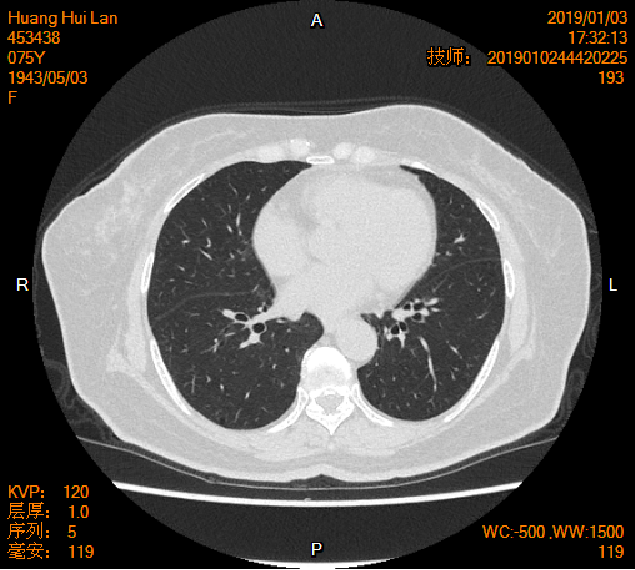

2019-01-04胸腹盆CT